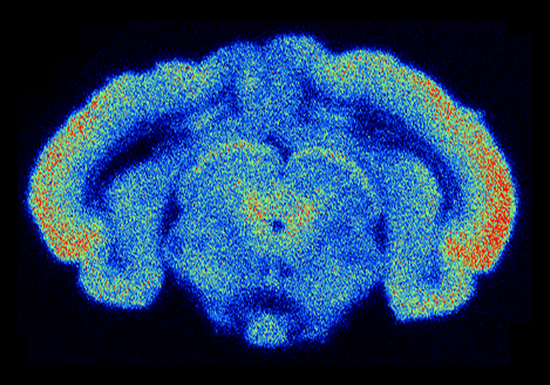

Figure 11.8 : Liaison de[3H]5-HT-moduline dans le cerveau de cobaye (au niveau du mésencéphale). Le signal a été acquis par le $\beta $-imager 2000, de la société biospace [59]. Image originale courtoisement fournie par Ana Cardona.

beta imager